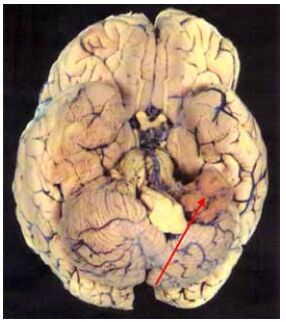

77 一位 55 歲女性患者因顱內腫瘤住院,該腫瘤的肉眼觀如圖示箭頭所指,則下列有關該腫瘤的敘述中, 何者最正確?

(A)是低度惡性的神經膠質瘤 (B)是成人最惡性的腦瘤 (C)會引發單側聽力喪失 (D)會引發雙側半盲